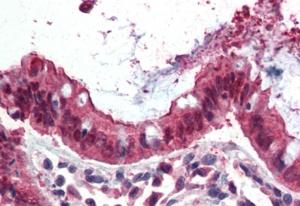

APG00110G (3.8 μg/ml) staining of paraffin embedded Human Small Intestine. Steamed antigen retrieval with citrate buffer pH 6, AP-staining. |